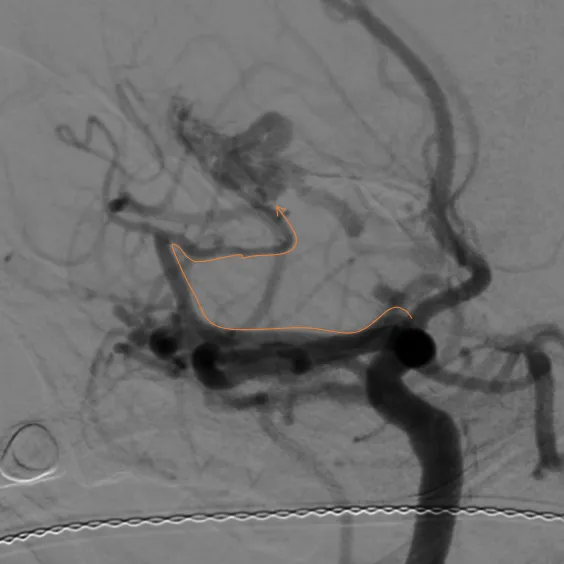

术前造影

左颈总造影,未见异常供血

右颈外造影,可见右侧蝶腭动脉分支供血,但无良好路径显示

右颈内造影,可见右侧眼动脉-筛后动脉供血,见经额底静脉-双侧额部皮层静脉向上矢状窦方向引流